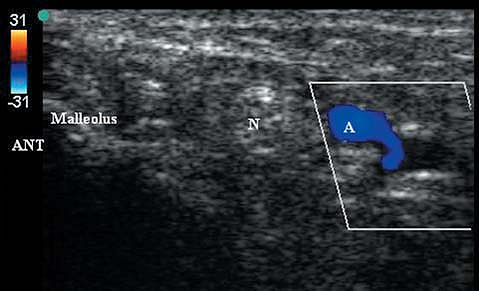

The medial malleolus is an hyperechoic curvilinear structure. The

posterior tibial artery and hyperechoic tibial nerve are found

posterior and superficial to the medial malleolar bony shadow (Figs. 42-2, 42-3).

Figure 42-2.

Sonogram (with color Doppler) of anatomy posterior to the medial malleolus. Ant, anterior; N, posterior tibial nerve; A, posterior tibial artery. |